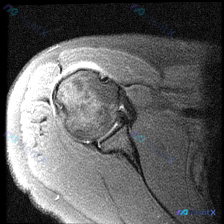

整理了一份肩关节MRI病例讨论材料,先放轴位T2加权像的分析。 核心发现: - 扫描层面在盂肱关节中部,显示肱骨头、关节盂、前后盂唇 - 前盂唇(图像左侧)可见明显不连续高信号,穿透盂唇结构 - 后盂唇形态完整,信号均匀;肩胛下肌、肱二头肌长头腱未见明显异常 讨论焦点:这个前盂唇病变更像真性撕裂(如...